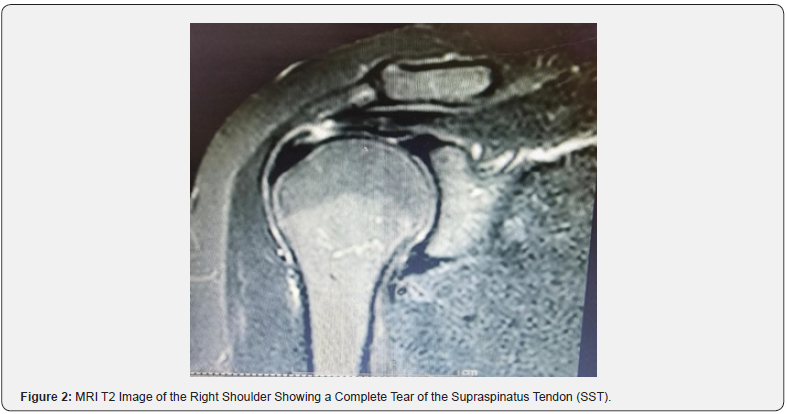

This section outlines the key performance metrics used to evaluate the accuracy of MRI in diagnosing rotator cuff injuries. True Positive (TP) refers to the number of cases where MRI correctly identified a tear, subsequently confirmed by surgery. In this sample, 91 cases were identified as true positives, demonstrating a high capability of MRI to detect tears accurately. A T2-weighted MRI scan of the right shoulder demonstrates a complete tear of the supraspinatus tendon (SST). The image highlights the disrupted tendon fibers and associated fluid signal, which are hallmark features of a full-thickness tear. T2-weighted sequences are particularly effective in visualizing soft tissue injuries due to their ability to emphasize fluid accumulation and inflammation. This finding aligns with the surgical confirmation of rotator cuff injuries, reinforcing the high sensitivity of MRI in detecting full-thickness tears and its critical role in pre-surgical planning and clinical decision-making (see Figure 2 in the Appendix). Additionally, another T2-weighted MRI scan shows a partial tear of the supraspinatus tendon (SST), emphasizing the limitations of MRI in detecting partial-thickness tears. The image reveals subtle disruptions in tendon fibers with less pronounced fluid signal compared to full-thickness tears. Such findings highlight the diagnostic challenge of differentiating between partial and complete tears in MRI (see Figure 3 in the Appendix).